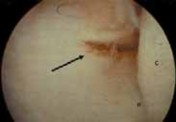

With the proximal medial portal as the standard viewing portal, the 30-degree scope is advanced just past the radial head to visualize the lateral joint capsule and undersurface of the ECRB origin ( TECH FIG 2A).

The capsule often adheres to the undersurface of the ECRB and can have varying degrees of degeneration, presenting as linear tears (type II lesion), fraying, or yellowish fatty infiltration, or it can have a thin, translucent appearance ( TECH FIG 2B).

The capsule and tendon may be completely avulsed and retracted; this is classified as a type III lesion ( TECH FIG 2C).

- C. Type III lesion showing complete avulsion and retraction of the lateral capsule and ECRB tendon. D. Fatty degeneration of the ECRB tendon ( arrow ), which is overlying the ECRL muscle–tendon. E. A 4.5-mm shaver is used for the initial débridement of the ECRB, which is in close proximity to the capitellum ( C ) and radial head ( R ). F. Débridement of the pathologic ECRB tendon and capsule with healthy-appearing extensor carpi radialis longus superficial. G. A 4.0-mm abrader is the final step to decorticate the